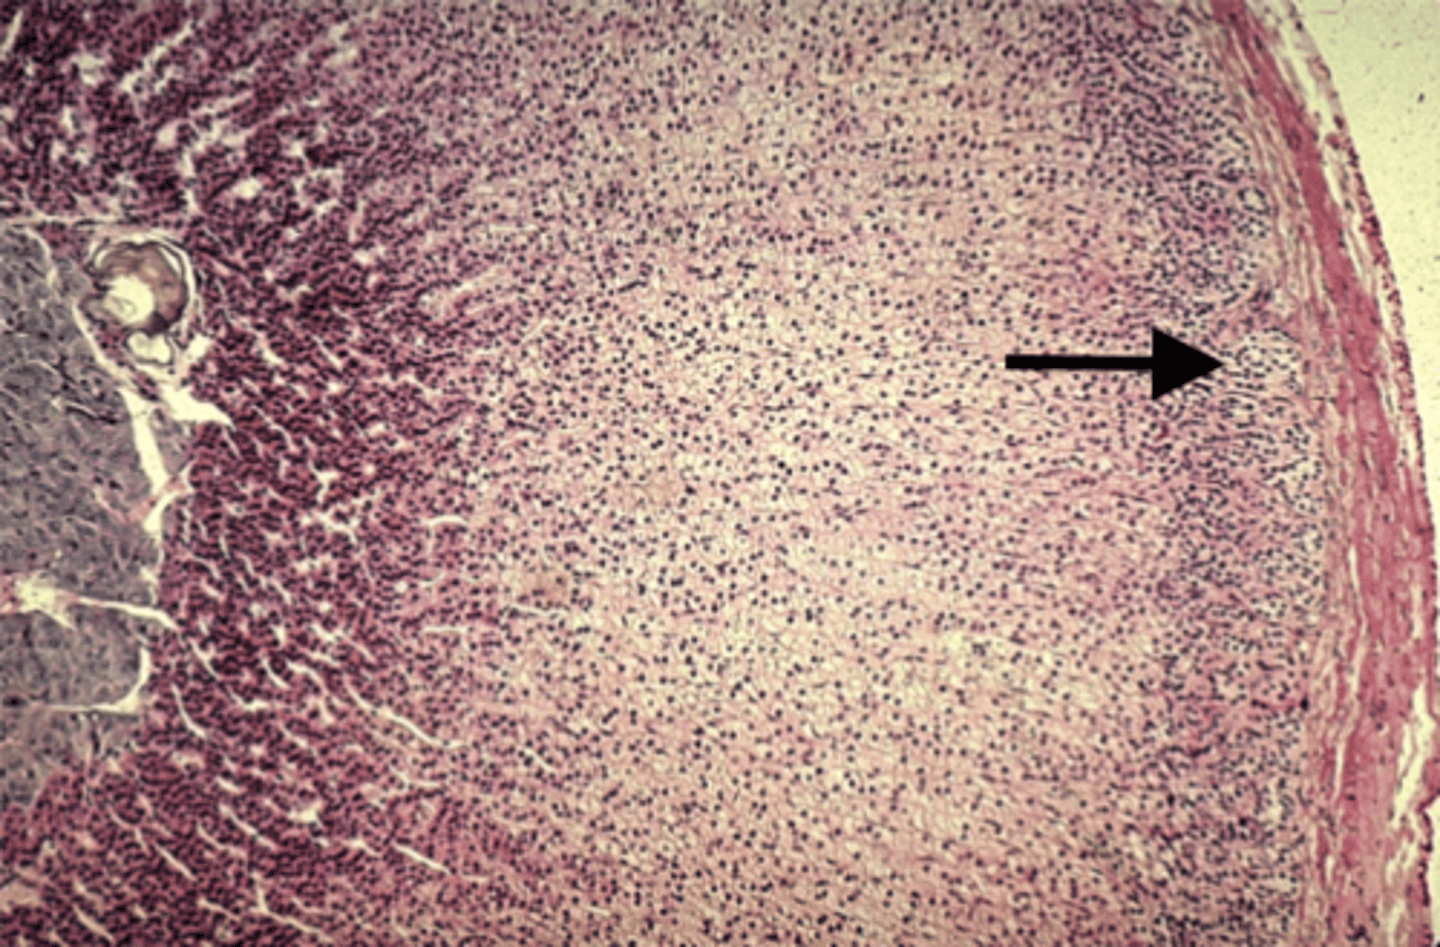

Adrenal gland

what is this?

Zona fasciculata

what is this pointing to?

Zona reticularis

what is this pointing to?

medulla

what is this pointing to?

Aldosterone

Zona glomerulosa secretes

Androgens

Zona reticularis secretes

Epinephrine

What hormone does the adrenal medulla secrete?

Cortisol

Zona fasciculata secretes

Zona glomerulosa

what is this pointing to?